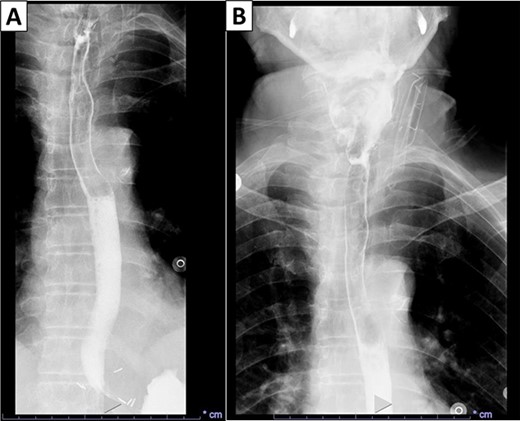

Gross examination revealed a fungating, exophytic, ulcerated, firm mass measuring 3.2 × 2.5 × 1 cm with a white cut surface involving the full thickness of the esophageal wall and grossly abutting the serosal surface. Microscopic examination showed a moderately differentiated SCC, invading the submucosa (Fig. 3). The surgical margins of resection were free of carcinoma and one cervical lymph node was identified and it showed no metastatic carcinoma. Postoperatively, the patient did well with no reported complications. An X-ray esophagogram was done showing no postoperative leak and no residual ZD (Fig. 4). He was referred to a hemato-oncologist for further management.

X-ray esophagogram performed postoperatively. No postoperative leak and no residual ZD were seen.

The first case of SCC arising in ZD was described by Halstead et al. in 1904 [12]. To make a definitive diagnosis, surgical excision and microscopic examination are needed. High clinical suspicion is paramount to detect a malignant transformation. In our case, the patient had a history of over 6 years of ZD, and suddenly the severity and frequency of his symptoms worsened. The definitive treatment for ZD is excision. Smaller defects may be treated conservatively and assessed periodically to determine growth, velocity of growth and if the patient exhibits other concerning symptoms such as weight loss and aspiration. After surgery, patients can be evaluated for residual disease with an esophagogram. In our case, the imaging that was done after the surgery demonstrated no acute leak and no residual ZD.